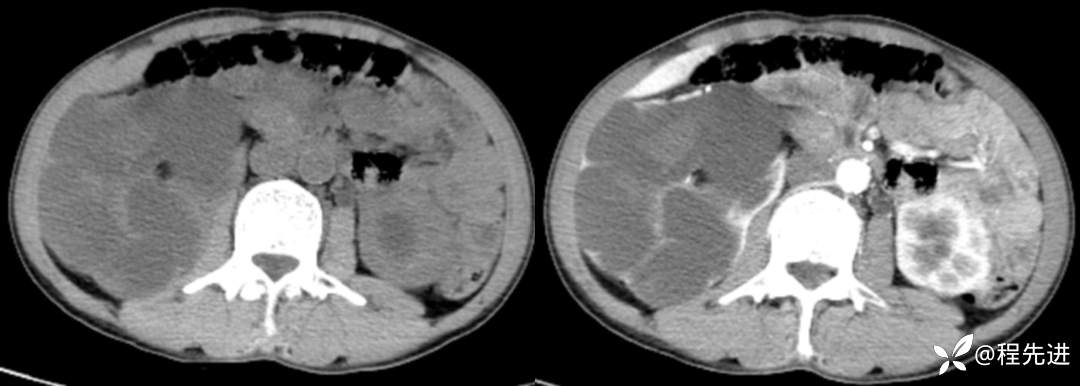

CT平扫+增强

左平扫,右增强